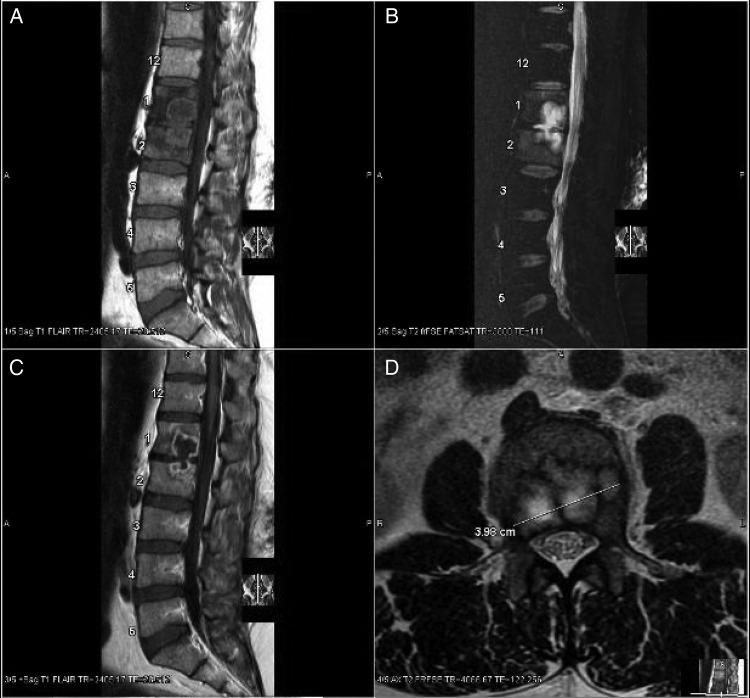

In persons with advanced immunosuppression, Mycobacterium avium complex (MAC) typically causes disseminated disease with systemic symptoms. We report 2 cases in which MAC caused localized osteomyelitis in human immunodeficiency virus (HIV)-infected individuals on antiretroviral therapy with rising CD4 counts. We summarize 17 additional cases of HIV-associated MAC osteomyelitis from the literature and compare CD4 count at presentation for vertebral cases versus nonvertebral cases, which reveals a significantly higher CD4 at presentation for vertebral cases (median 251 cells/µL vs 50 cells/µL; P = .043; Mann-Whitney U test). The literature review demonstrates that the majority of cases of MAC osteomyelitis, especially vertebral, occurs in individuals with CD4 counts that have increased to above 100 cells/µL on antiretroviral therapy. Among HIV-infected individuals with osteomyelitis, MAC should be considered a possible etiology, particularly in the setting of immune reconstitution.

在免疫抑制严重的患者中,鸟分枝杆菌复合体(MAC)通常会引起全身性症状的播散性疾病。我们报告了 2 例在接受抗逆转录病毒治疗且 CD4 计数升高的 HIV 感染者中,MAC 引起局部骨髓炎的病例。我们总结了文献中另外 17 例 HIV 相关 MAC 骨髓炎的病例,并比较了脊柱病例和非脊柱病例的 CD4 计数,结果显示脊柱病例的 CD4 计数显著更高(中位数 251 个/µL 与 50 个/µL;P =.043;Mann-Whitney U 检验)。文献回顾表明,大多数 MAC 骨髓炎病例,尤其是脊柱病例,发生在 CD4 计数在抗逆转录病毒治疗后升高至 100 个/µL 以上的患者中。在患有骨髓炎的 HIV 感染者中,应考虑 MAC 为可能的病因,尤其是在免疫重建的情况下。